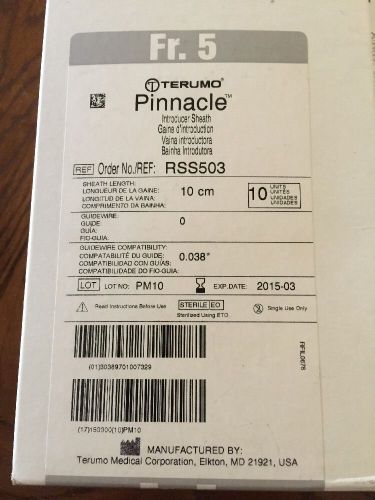

Terumo Pinnacle-10CM Fr. 5 RSS503 BOX OF 10 Nib Exp 3-2015